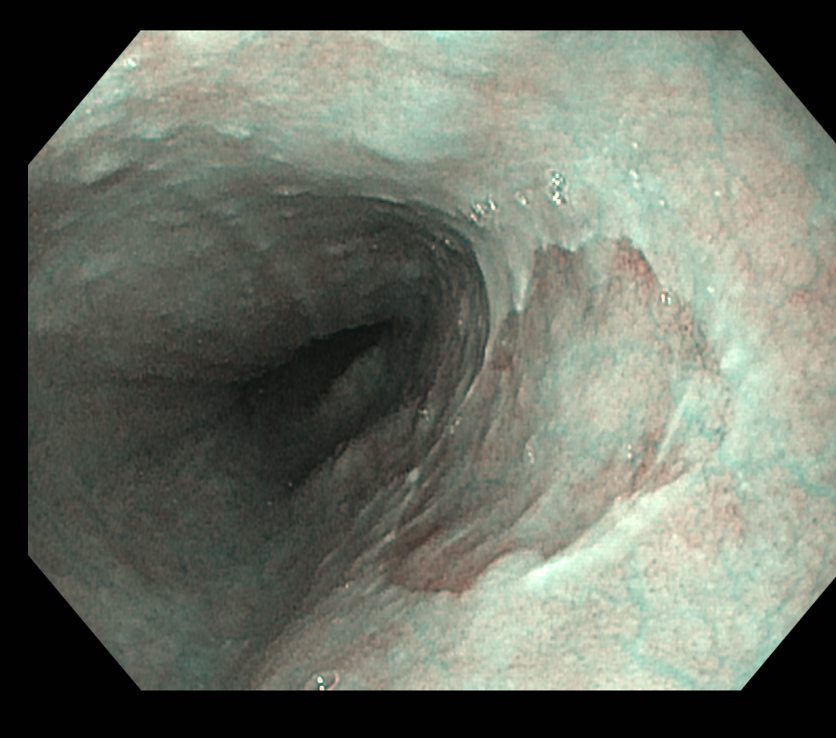

식도 상부에서 전형적으로 발견되는 위점막과 닮은 구별되는 영역. 일반 인구에서 유병률은 autopsy에서 약 5%인 반면 위내시경 연구에서는 상부위장관내시경을 시행하는 환자에서 0.4~11%. 내시경 연구에서 유병률이 더 낮은 이유는 inlet patches가 식도 상부에 위치하고 있기 때문인 것 같습니다. 가장 일반적으로는 UES 아래 식도 3 cm 부위에서 발견되며 이 부위는 일반적인 상부위장관내시경 동안에 잘 보여지는 곳은 아닙니다. Inlet patches는 모든 연령에서 기술되었지만 가장 일반적으로 발견되는 나이는 50대 중반입니다.